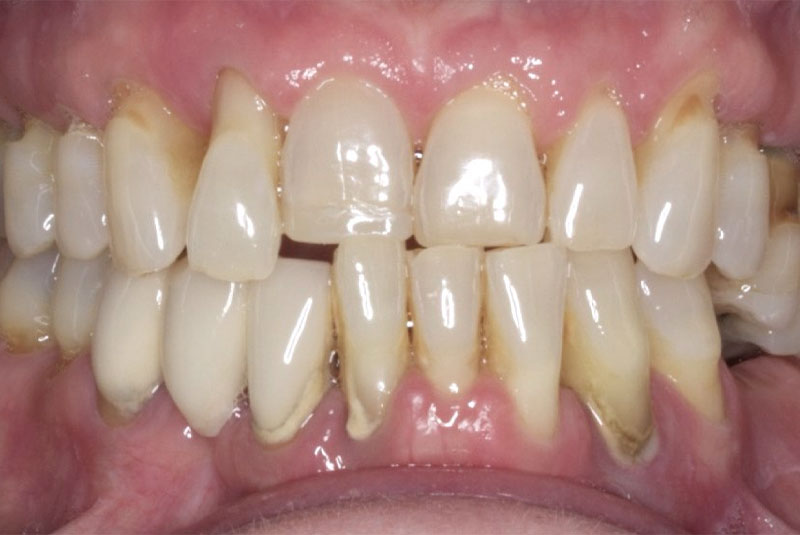

The patient had her implants placed 20 years ago. Four implants, particularly in the maxilla, were not positioned ideally for me to utilize and restore, while the four implants in the mandible were outdated and no longer functional. The patient's primary concern is to restore both function and aesthetics.

Before & After Veneers (#6,8,9,10,11,12) Crowns (23,24,25,26) Bridge (#27-28p-29), Overlay #21, Implant & Implant Crowns (#7,13,14,15,18,19,20,22), Composite (#3,4,5,12)